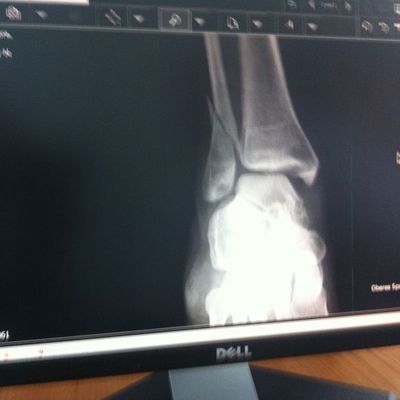

Fehlstelung verheilte Fibula Reoperation: 06.05.2011

Diagnose: in fehlstelung verheilte fibula und instabile malleolengabel 4 monate nach malleolar- luxationsfraktura rechts. operation: 06.05.2011 metallentfernug der fibula (platte=schrauben) mediale arthotomie zur narbenextraktion korrigierende (varisierende und verlängernde ) osteotomie des assenknöchels stabilisation mit winkelstabiler platte (